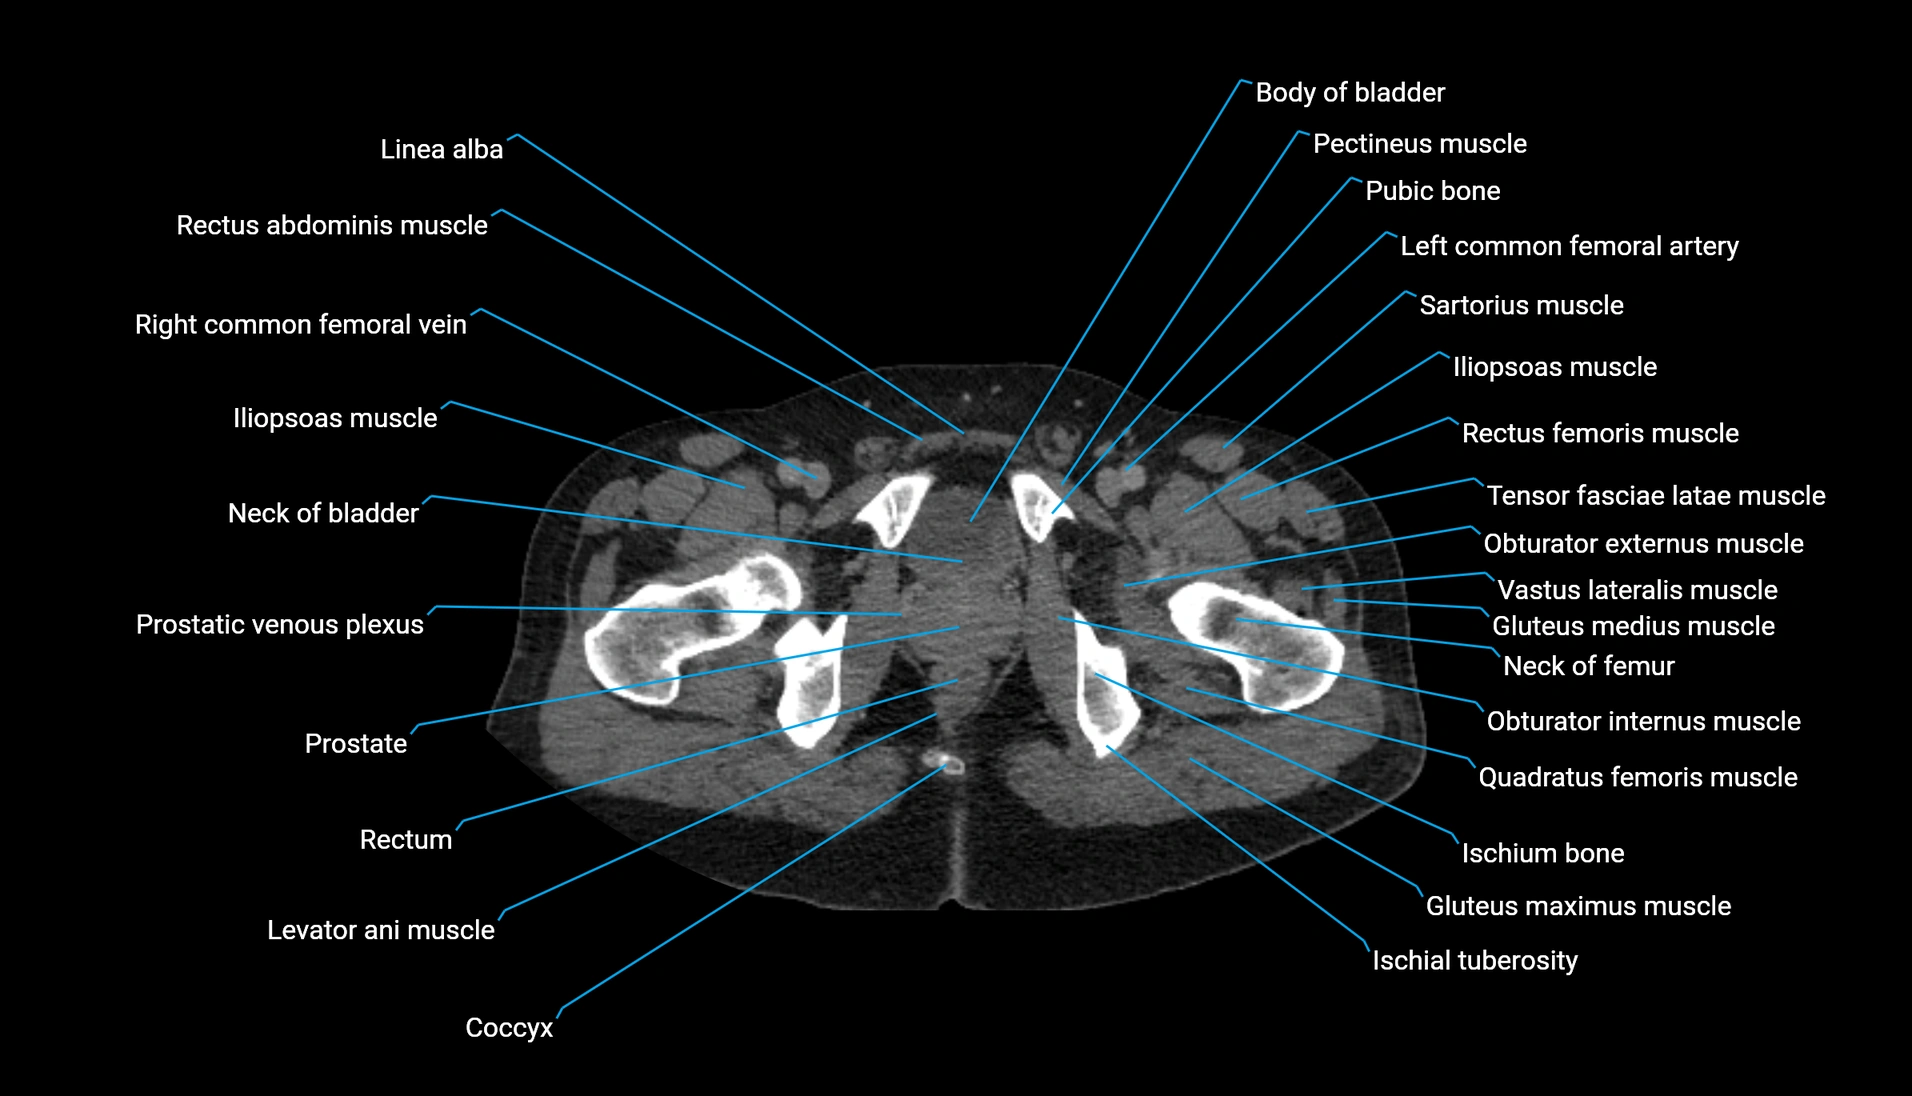

CT Appearance

Non-contrast CT:

-

Demonstrates cortical bone of acetabular rim in excellent detail

Detects fractures, dysplasia, retroversion, or bony overcoverage (pincer impingement)

3D reconstructions used in preoperative hip surgery planning

CT VRT 3D image

CT image